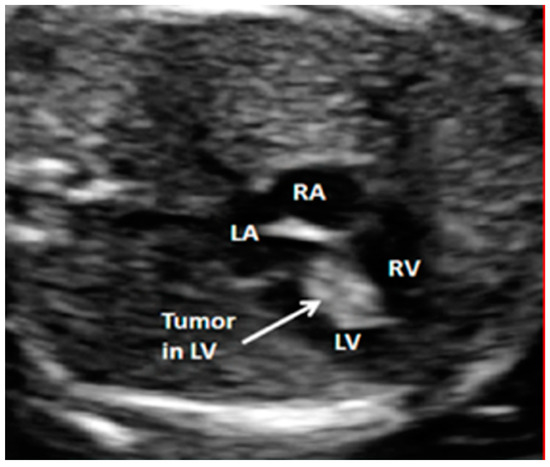

3. Pharmacological Approach to Treatment of Intracardiac Rhabdomyomas